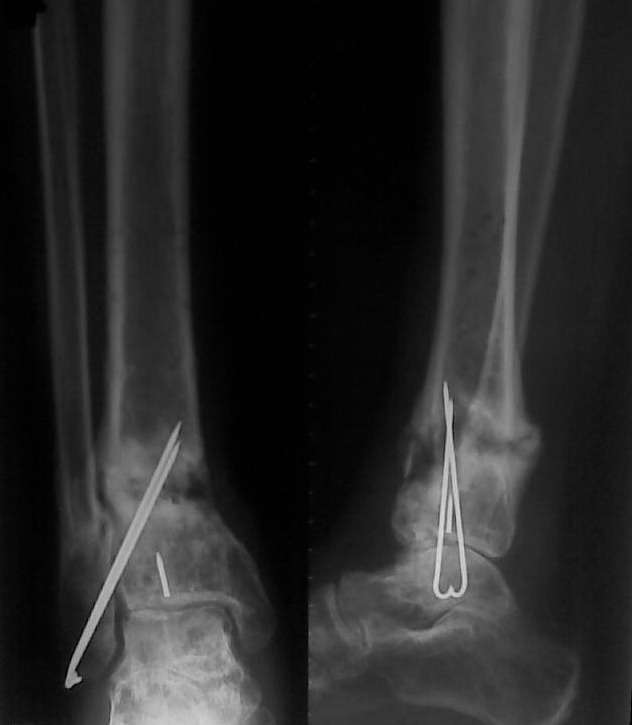

Уважаемые коллеги, обратилась больная 30 года, травма 1 год назад,

открытый перелом дистального метаэпифиза левой голени, закрытый

перелом левой таранной кости, закрытый перелом наружной лодыжки слева.

Больная была прооперирована в солидном лечебном учреждении был

произведен остеосинтез переломов (снимков пока нет).

Послеоперационный период осложнился нагноением, конструкции были

удалены. На сегодняшний день имеется следующее: по

переднее-медиальной поверхности имеется свищ около 5 мм в диаметре с

небольшим количеством гнойного отделяемого, конечность опорна, боли

при нагрузке практически нет. Нервно - сосудистый статус без

патологии. Подошвенное сгибание 10, тыльное 8 градусов. Снимки

представлены ниже. Как лучше поступить в данном случае? имеется 2

варианта:

1.Удалить спицы, качественная секвестрнекрэктомия, лаваж полости с

последующим заполнением её цементными бусами с антибиотиком. С целью

профилактики перелома наложить простейший АВФ из двух колец. Через

2-4 недели (при благоприятном течении процесса) удалить бусы и

заполнить полость аутографтом. Что смущает при этом варианте: малый

размер полости 20 х 30 мм - мало цемента с антибиотиком -

недостаточная концентрация антибиотика. Кроме того, дефект расположен

вблизи сустава, где существует малое количество мягких тканей.

Смущает так же состояние таранной кости.

2. Выполнить  резекцию очага с последующим замещением дефекта по

Илизарову. Больная и родственники не совсем в восторге от этого

варианта (длительные сроки, неудобства, связанные с ношением АВФ).

Хотя  возможно это и лучший вариант. Про таран уже говорилось выше.

Какие ещё возможны варианты ?